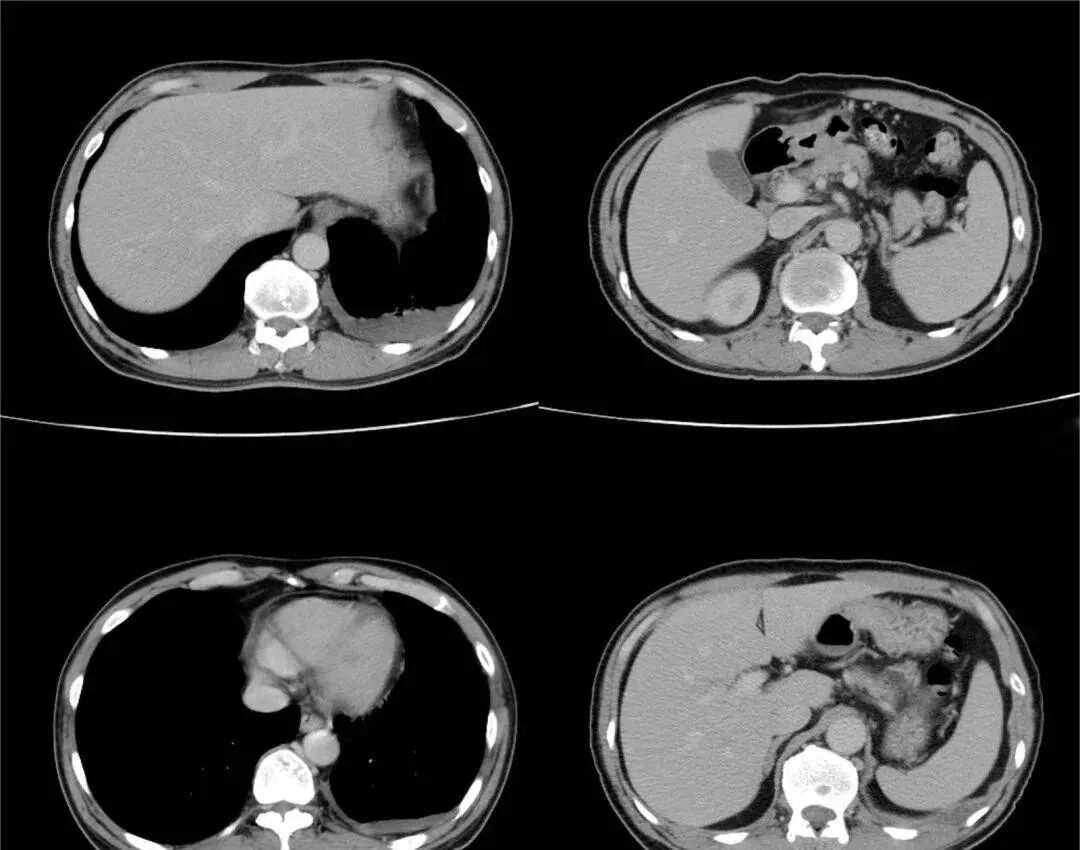

王先生为此走访了很多专家医生,医生建议除了定期复查外,需提高自身免疫力。王先生通过朋友推荐使用了一个疗程的免疫细胞应用。治疗几个月后,王先生再次复查,很神奇,肺结节不见了。

图片